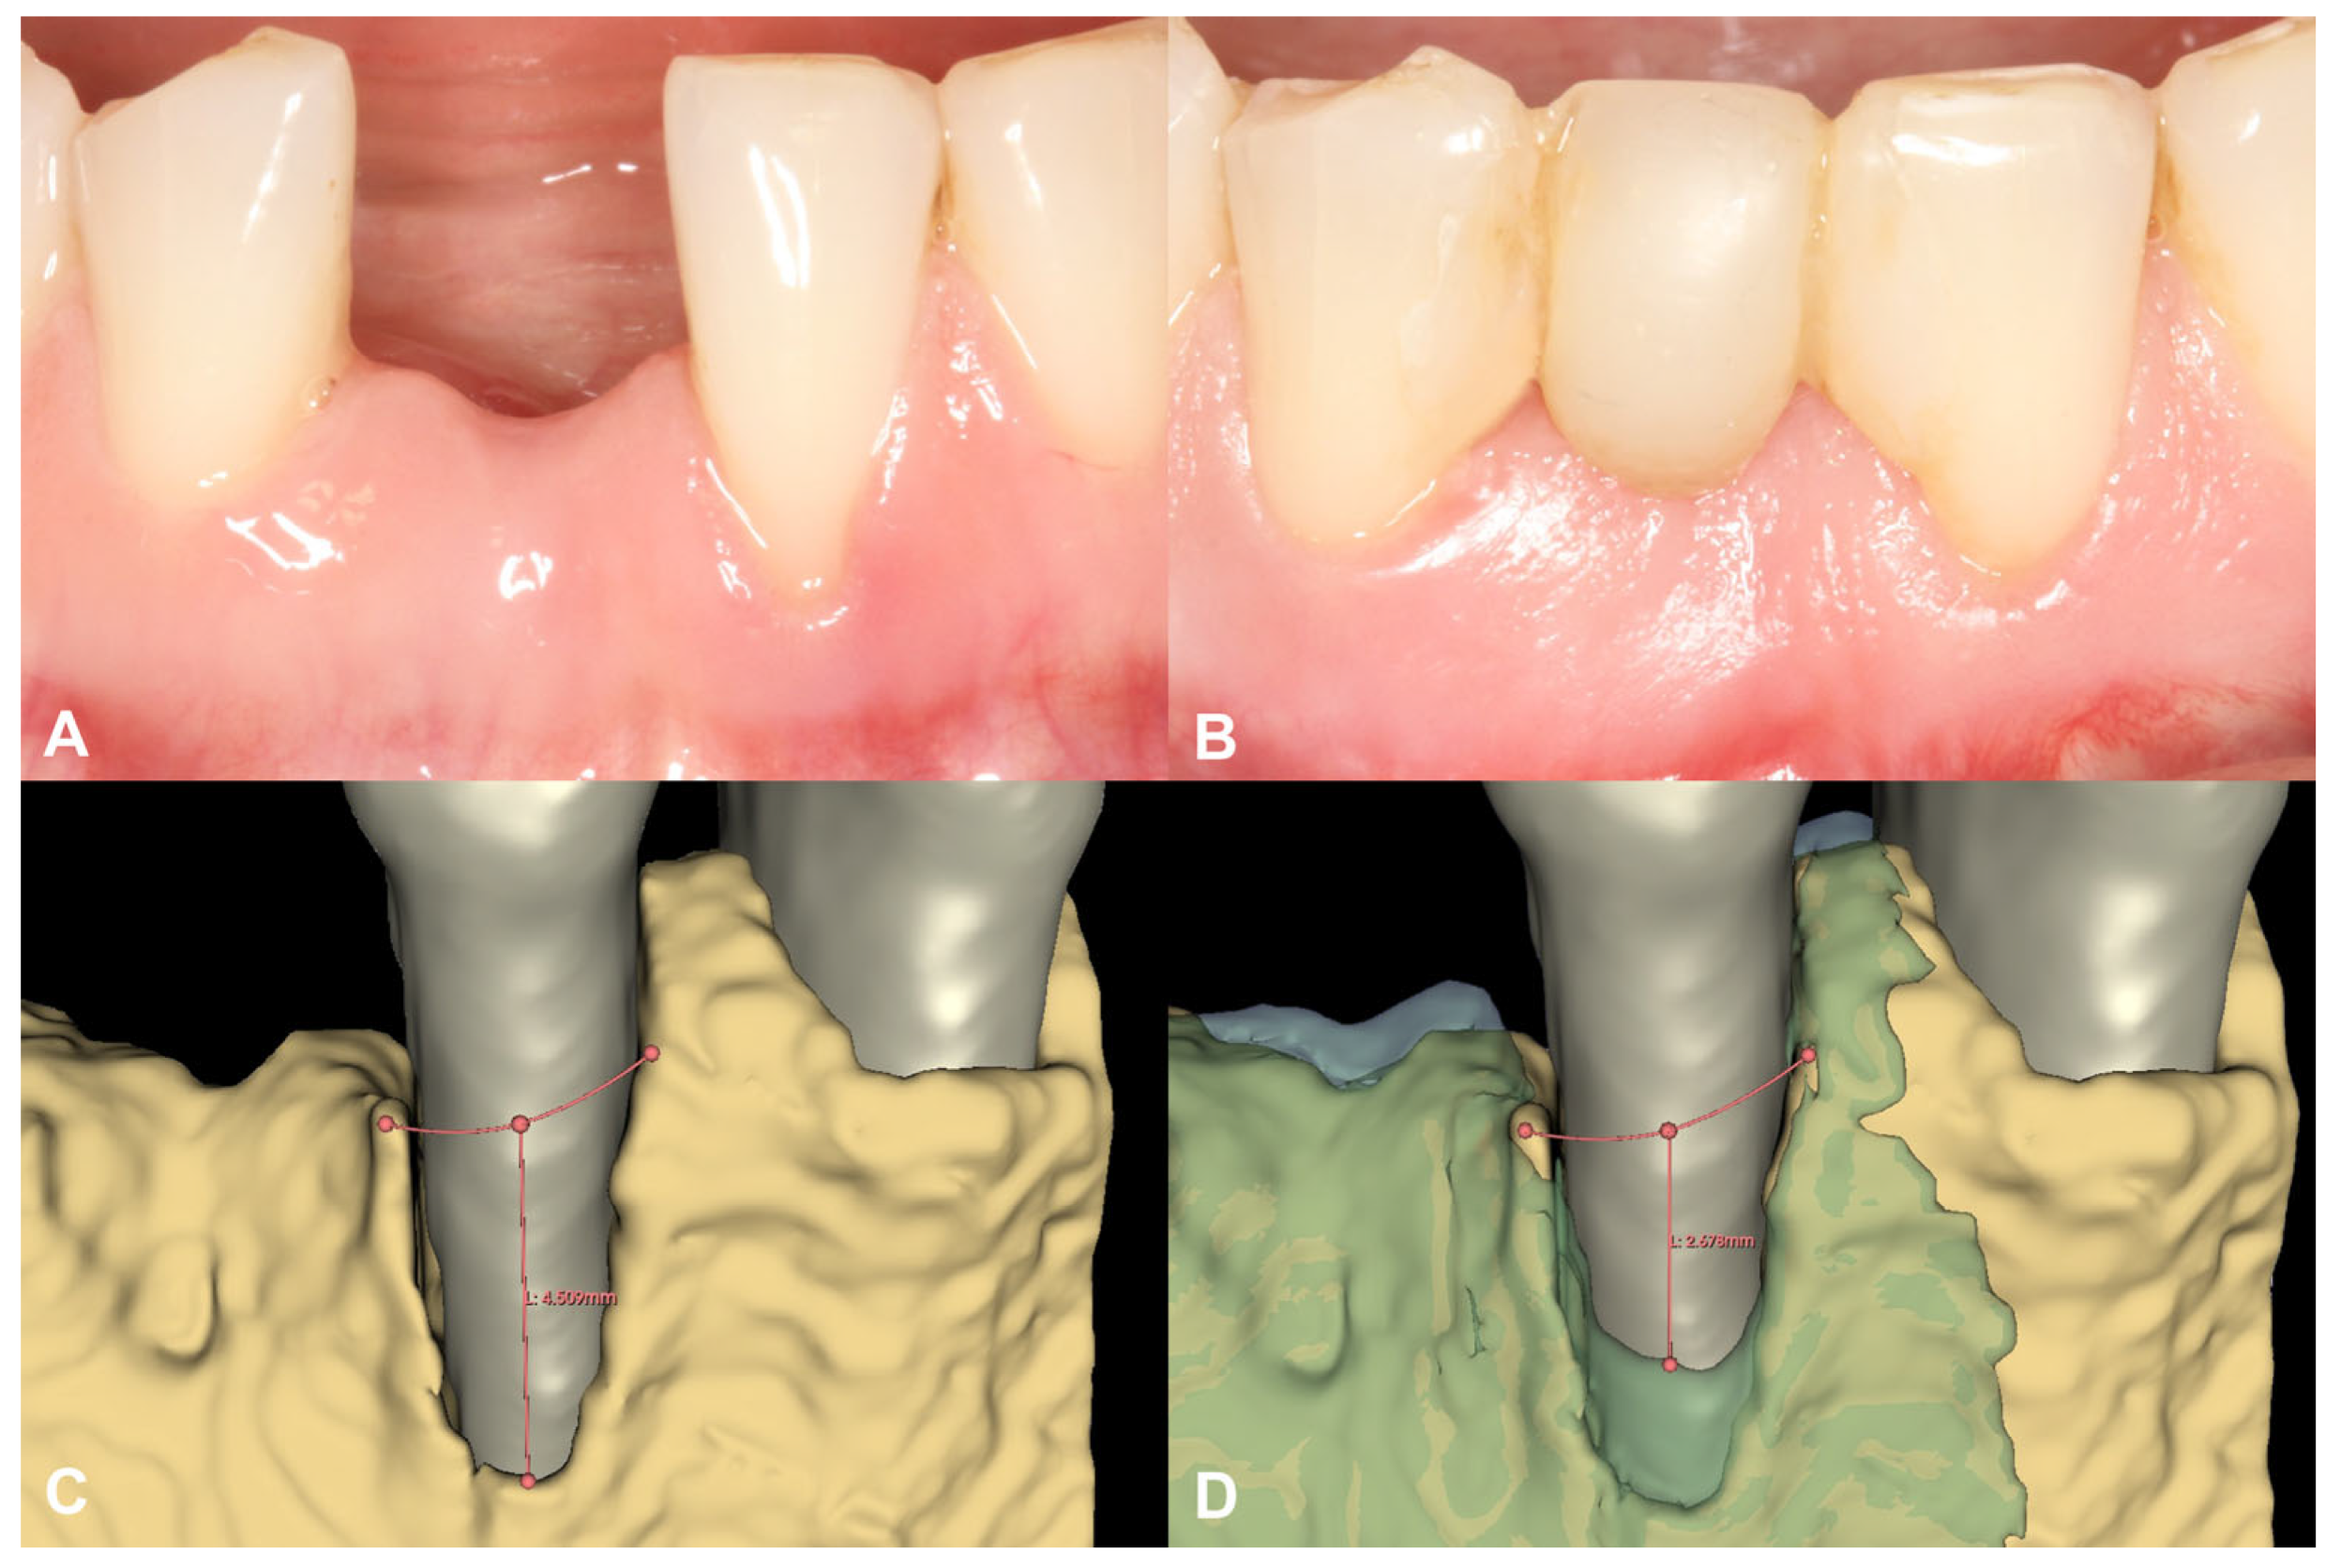

3.1. Case #1

3.1.1. Baseline Clinical Situation

3.1.2. Short-Term Hard Tissue Gain and Two-Year Follow-Up